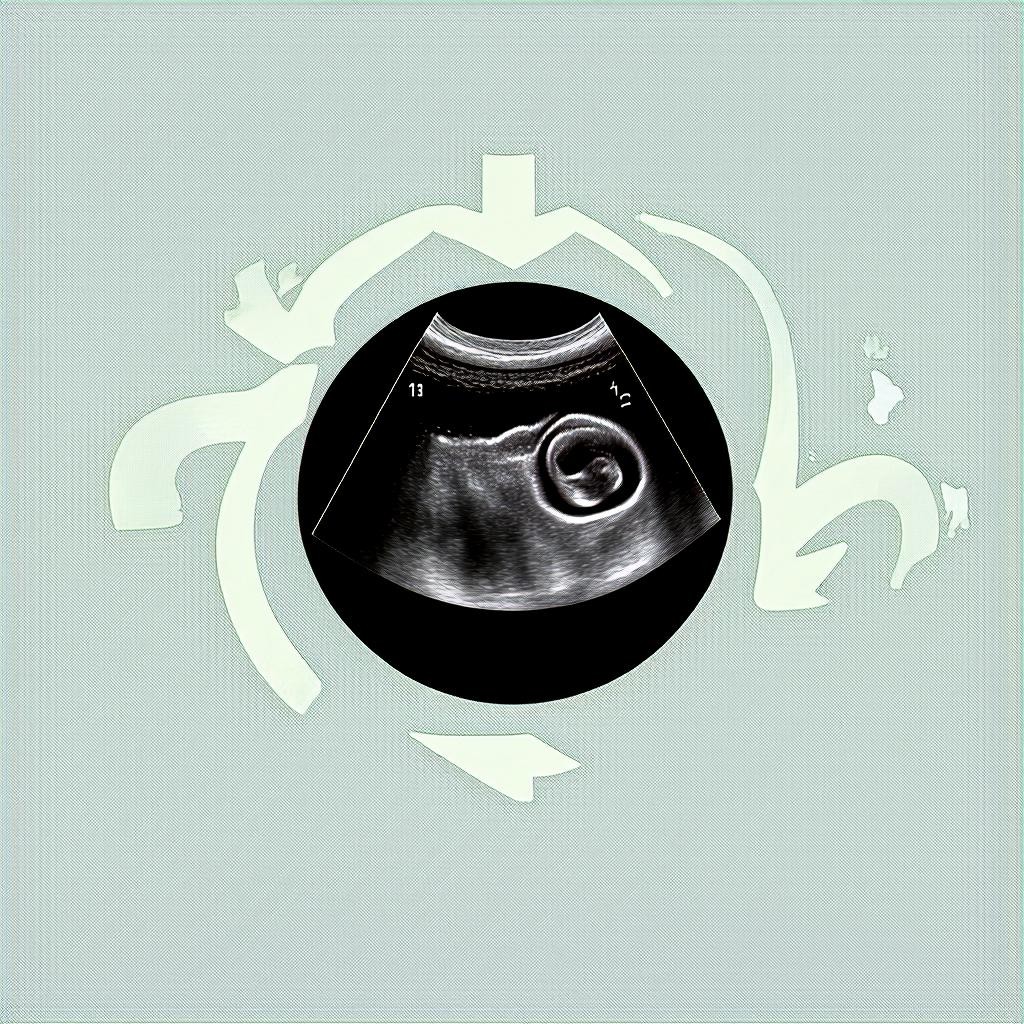

Что можно увидеть на УЗИ на 3 неделе?

На этом сроке эмбрион еще слишком мал, поэтому основная цель УЗИ — подтвердить факт беременности и исключить патологии. Вот что может показать исследование:

• Плодное яйцо — на 3 неделе оно может быть едва заметным, размером около 2-3 мм.

Важно понимать, что на таком раннем сроке даже современное оборудование не всегда может точно визуализировать эмбрион. Если врач не увидел плодное яйцо, это не всегда означает отсутствие беременности — возможно, срок еще слишком мал.

На 3 неделе беременности чаще всего используется трансвагинальное УЗИ. Этот метод позволяет получить более четкое изображение благодаря близкому расположению датчика к матке. Процедура безопасна и не причиняет вреда эмбриону.